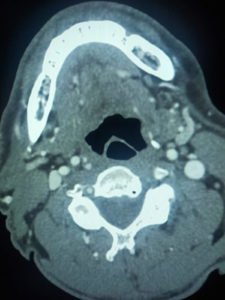

CT head was performed on arrival, showing no acute issues.

However, clinical suspicion of a posterior circulation stroke led to the activation of the Tele Stroke pathway.

The infusion was promptly halted, and a CT head was ordered to investigate the possibility of hemorrhagic transformation, which yielded negative results.

Despite these efforts, a subsequent CT angiogram revealed extensive basilar and vertebral thrombosis, leading to consideration for thrombectomy.